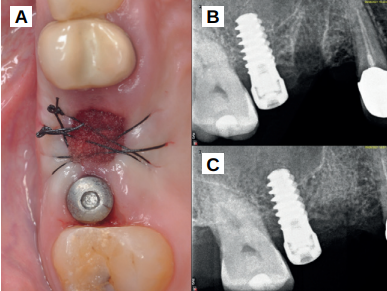

Tras la preparación del injerto, se procedió a su colocación en el alveolo del 1.5, usándose para cubrir el injerto una esponja hemostática (Proclinic, Madrid, España) y se suturó mediante un punto simple y un punto colchonero horizontal con sutura no reabsorbible de 4/0 (Supramid®, B. Braun, Barcelona, España), realizando una radiografía periapical paralelizada en el postoperatorio inmediato, así como un CBCT, para verificar la colocación adecuada del biomaterial en el alveolo post-extracción (Figuras 5 y 6).

A los 15 días se retiraron los puntos de sutura, apreciándose un buen aspecto de los tejidos blandos y la presencia de fibrina sellando la herida (Figura 7). Tras tres meses de cicatrización se comprobó su evolución mediante CBCT, apreciándose el mantenimiento de las dimensiones óseas en comparación con el escáner realizado antes de la extracción (Figura 8).

Se apreció un hueso de aspecto vital, sangrante y bien corticalizado. Se tomó una biopsia de tejido duro de 7 mm de profundidad por 3 mm de diámetro, mediante trefina, y se solicitó un análisis histomorfométrico. (Figuras 9 y 10).

Tras la biopsia se colocó un implante bone level Naturactis de ETK® (ETK Implants S.L, Sant Boi de Llobregat, España) (Figura 11) y se procedió al análisis histomorfométrico, apreciándose hueso esponjoso vital, en íntimo contacto con material dentinario (Figuras 12 y 13).